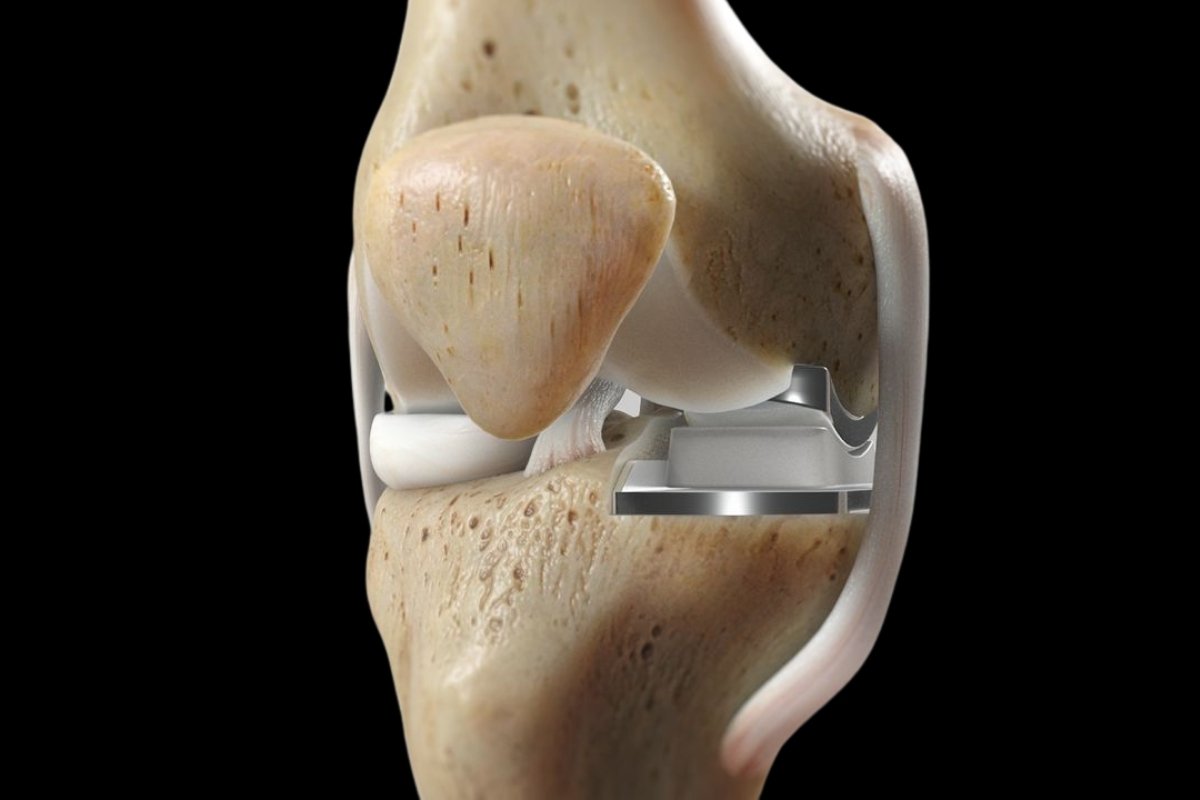

Partial Knee Replacement in Ahmedabad (also known as unicompartmental knee arthroplasty) is a surgical procedure where only the damaged portion of the knee joint is replaced with a prosthetic implant. This allows the healthy parts of the knee, including the ligaments and surrounding bone, to remain untouched, preserving more of your natural joint structure and movement.

Unlike a Total Knee Replacement, this procedure targets specific damage caused by localized arthritis or injury, making it less invasive and offering a quicker recovery with a more natural knee feel.

Only the damaged knee compartment is resurfaced

Preserves healthy bone, tissue, and ligaments